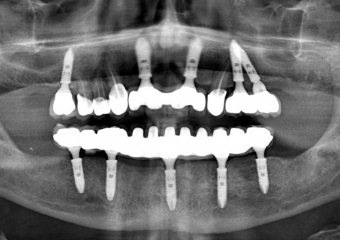

Raio X final com próteses fixas instaladas